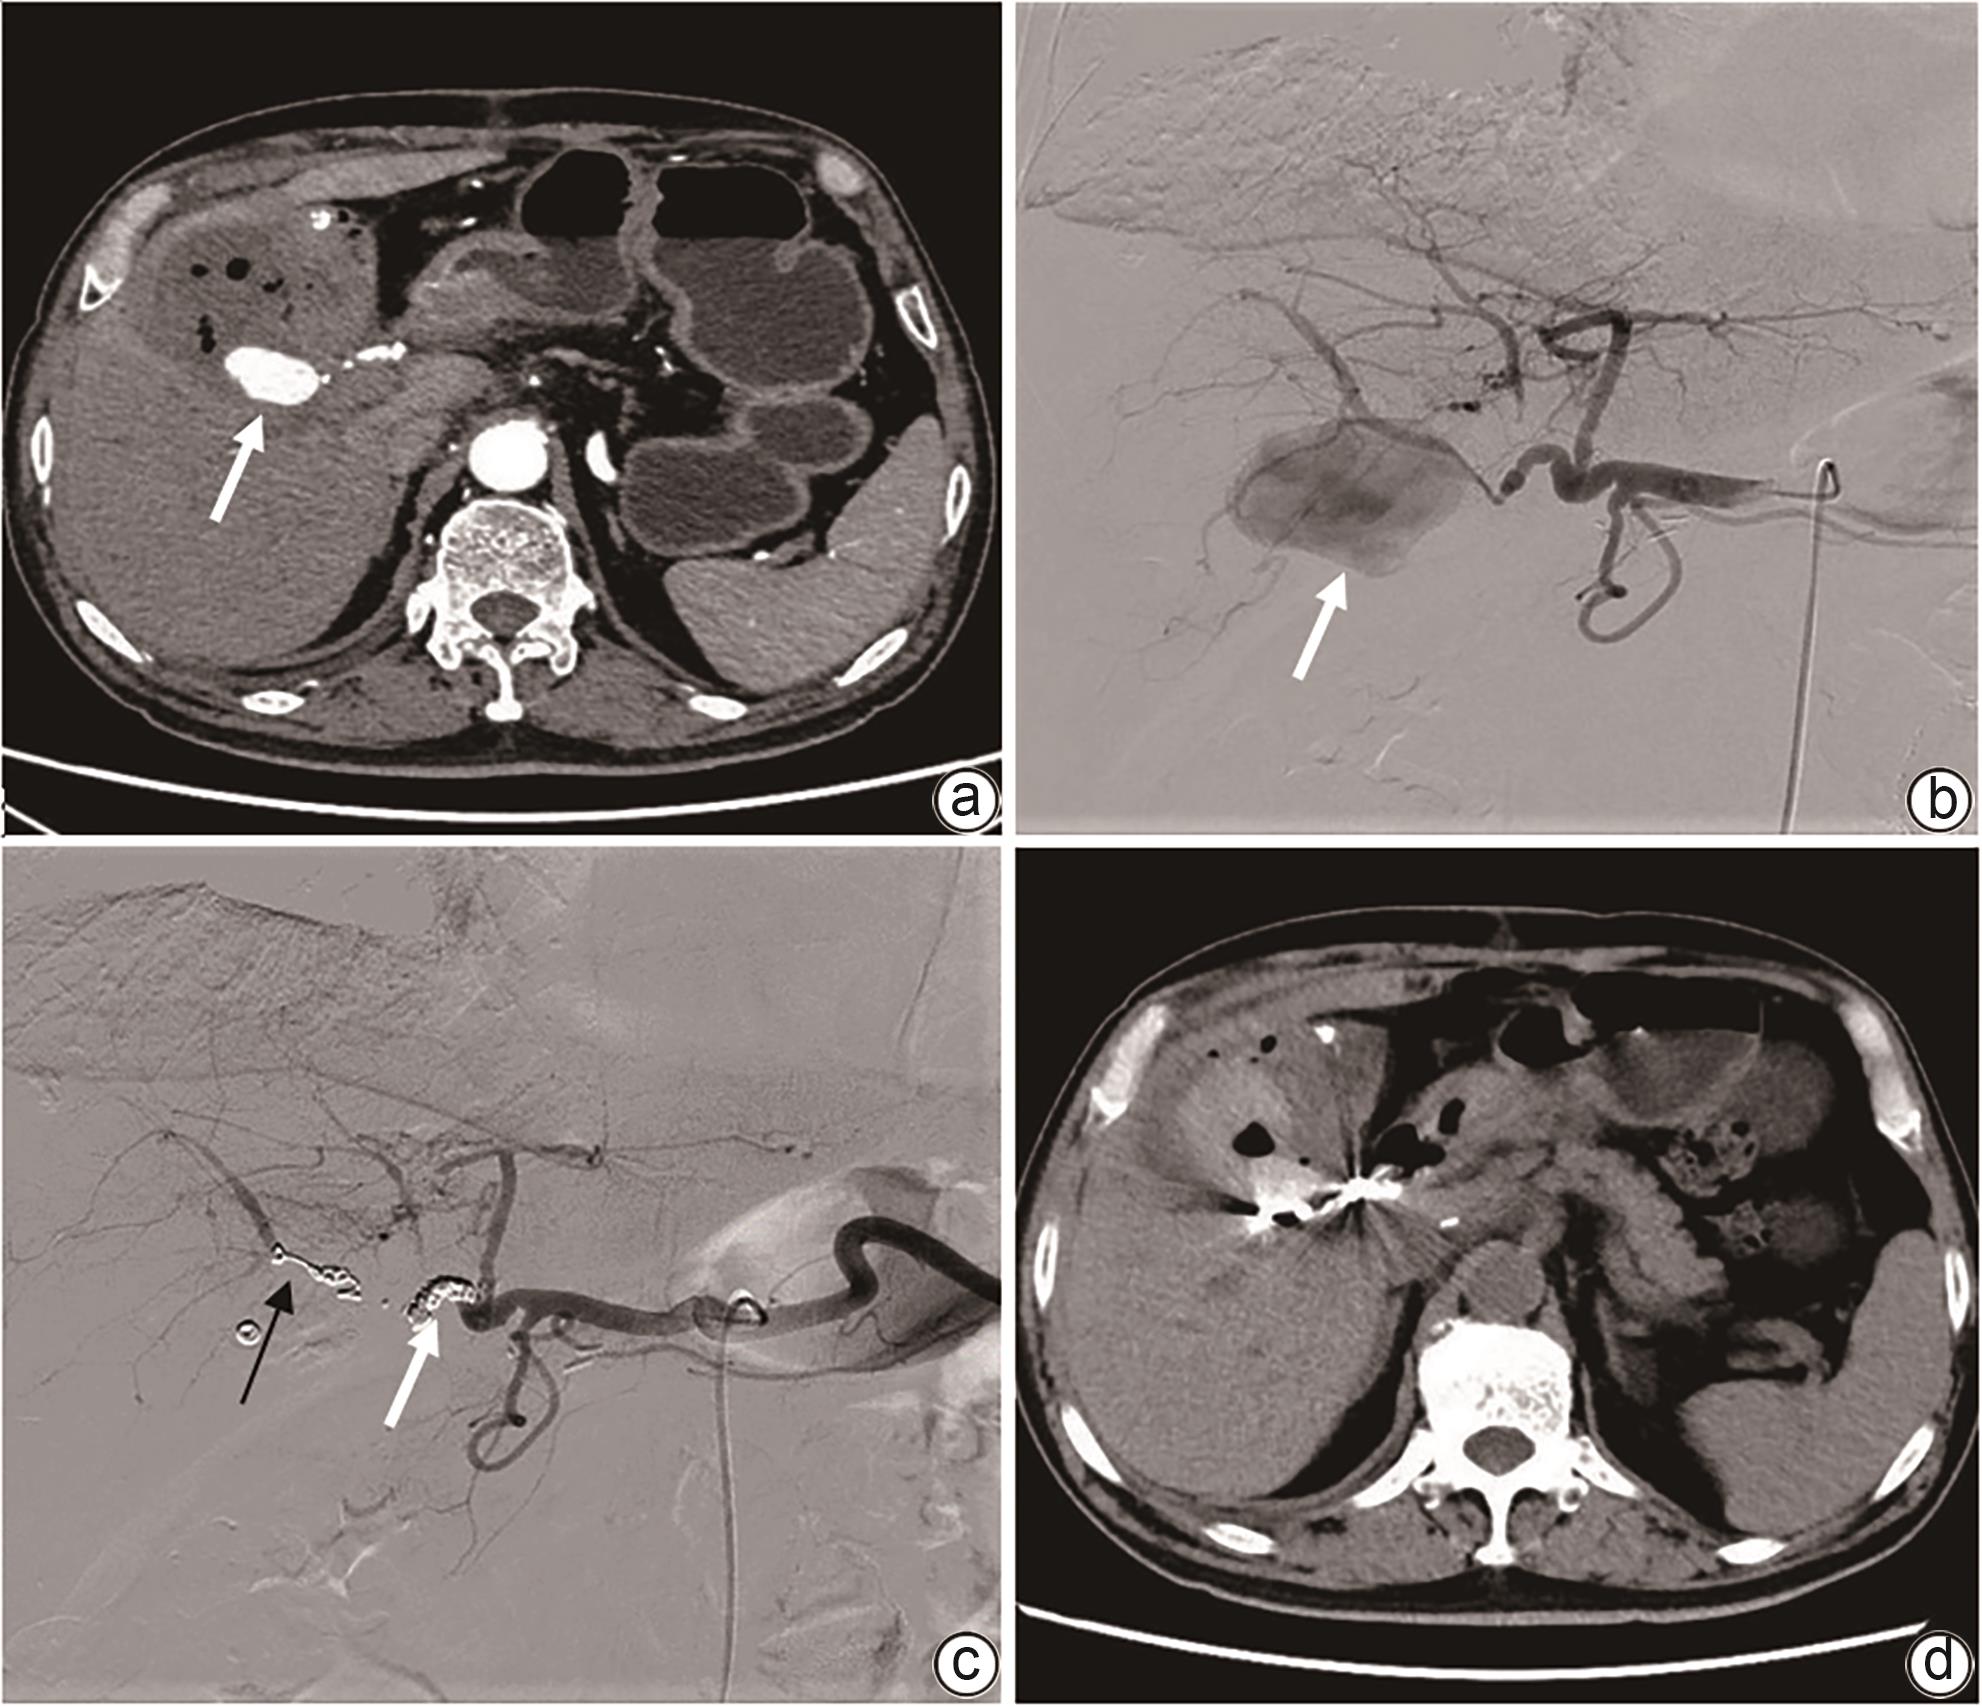

Imaging features and therapeutic strategies for lethal iatrogenic hemobilia

Chen WANG, Min WANG, Ke ZHANG, Jinxing ZHANG, Li LIU, Zhining FAN

2024, 40(10): 2070-2074. DOI: 10.12449/JCH241022

Abstract(1032) HTML (357) PDF (2026KB)(84)

Abstract:

Objective  To investigate the imaging features and pathogenesis of lethal iatrogenic hemobilia (LIH) and the value of transarterial intervention in the treatment of LIH.  Methods  A total of 269 patients with upper gastrointestinal bleeding who were admitted to The First Affiliated Hospital of Nanjing Medical University from August 2009 to July 2023 were enrolled, among whom 24 had a confirmed diagnosis of LIH and received treatment, and a retrospective analysis was performed for the clinical data of these 24 patients, including the iatrogenic causes, angiographic findings, and arterial interventions of LIH. Among the 24 patients, 23 received transarterial embolization (TAE) with gelatin sponge particles and coils, and 1 received a covered stent for isolation. The main criteria for assessing treatment outcome included the technical success rate of surgery, procedure-related complications, and long-term clinical follow-up.  Results  Among the 24 patients with LIH, 12 had LIH caused by interventional procedures, and 12 had LIH caused by hepatobiliary and pancreatic surgery. The main clinical manifestations included a significant reduction in blood pressure or a persistent reduction in hemoglobin in 13 patients and upper gastrointestinal bleeding in 18 patients. Among the 24 patients, 2 developed symptoms during surgery, 4 developed symptoms within 24 hours, and 18 developed symptoms after 24 hours. Angiography showed a positive bleeding rate of 100% (24/24), and imaging findings included pseudoaneurysms in 15 patients, hepatic artery truncation in 3 patients, extravasation of contrast medium in 5 patients, and hepatic arteriobiliary fistula in 3 patients. Among the 24 patients, 23 received TAE and 1 received stent implantation. Successful hemostasis was achieved for 23 patients, with a technical success rate of 95.8% (23/24). Four patients developed hepatic necrosis and abscess after TAE, and there was no rebleeding or recurrence after hemostatic treatment.  Conclusion  Various iatrogenic injuries may result in LIH with diverse clinical and imaging findings, and integrated diagnostic imaging combined with transarterial intervention is the best effective life-saving measure for LIH.